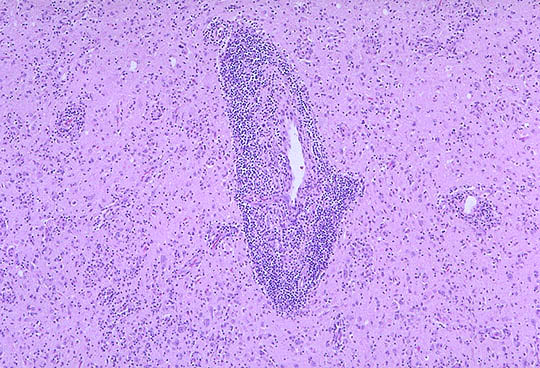

Correlation 4: EncephalitisObserve the many dark blue cells at low power magnification that have accumulated around the large blood vessel and in the surrounding brain. Normal brain tissue is composed of the gray matter with neurons, neuronal processes (axons, dendrites), and supporting glial cells, and of the white matter, which is predominantly axonal processes. When an infection involves the brain, then there are inflammatory cells that accumulate in order to fight the infection. Most infections that involve the brain itself (gray and white matter) are caused by viruses (such as West Nile virus). The inflammatory response to viral infections consists mainly of lymphocytes. These cells infiltrate around blood vessels and extend into the brain parenchyma. |